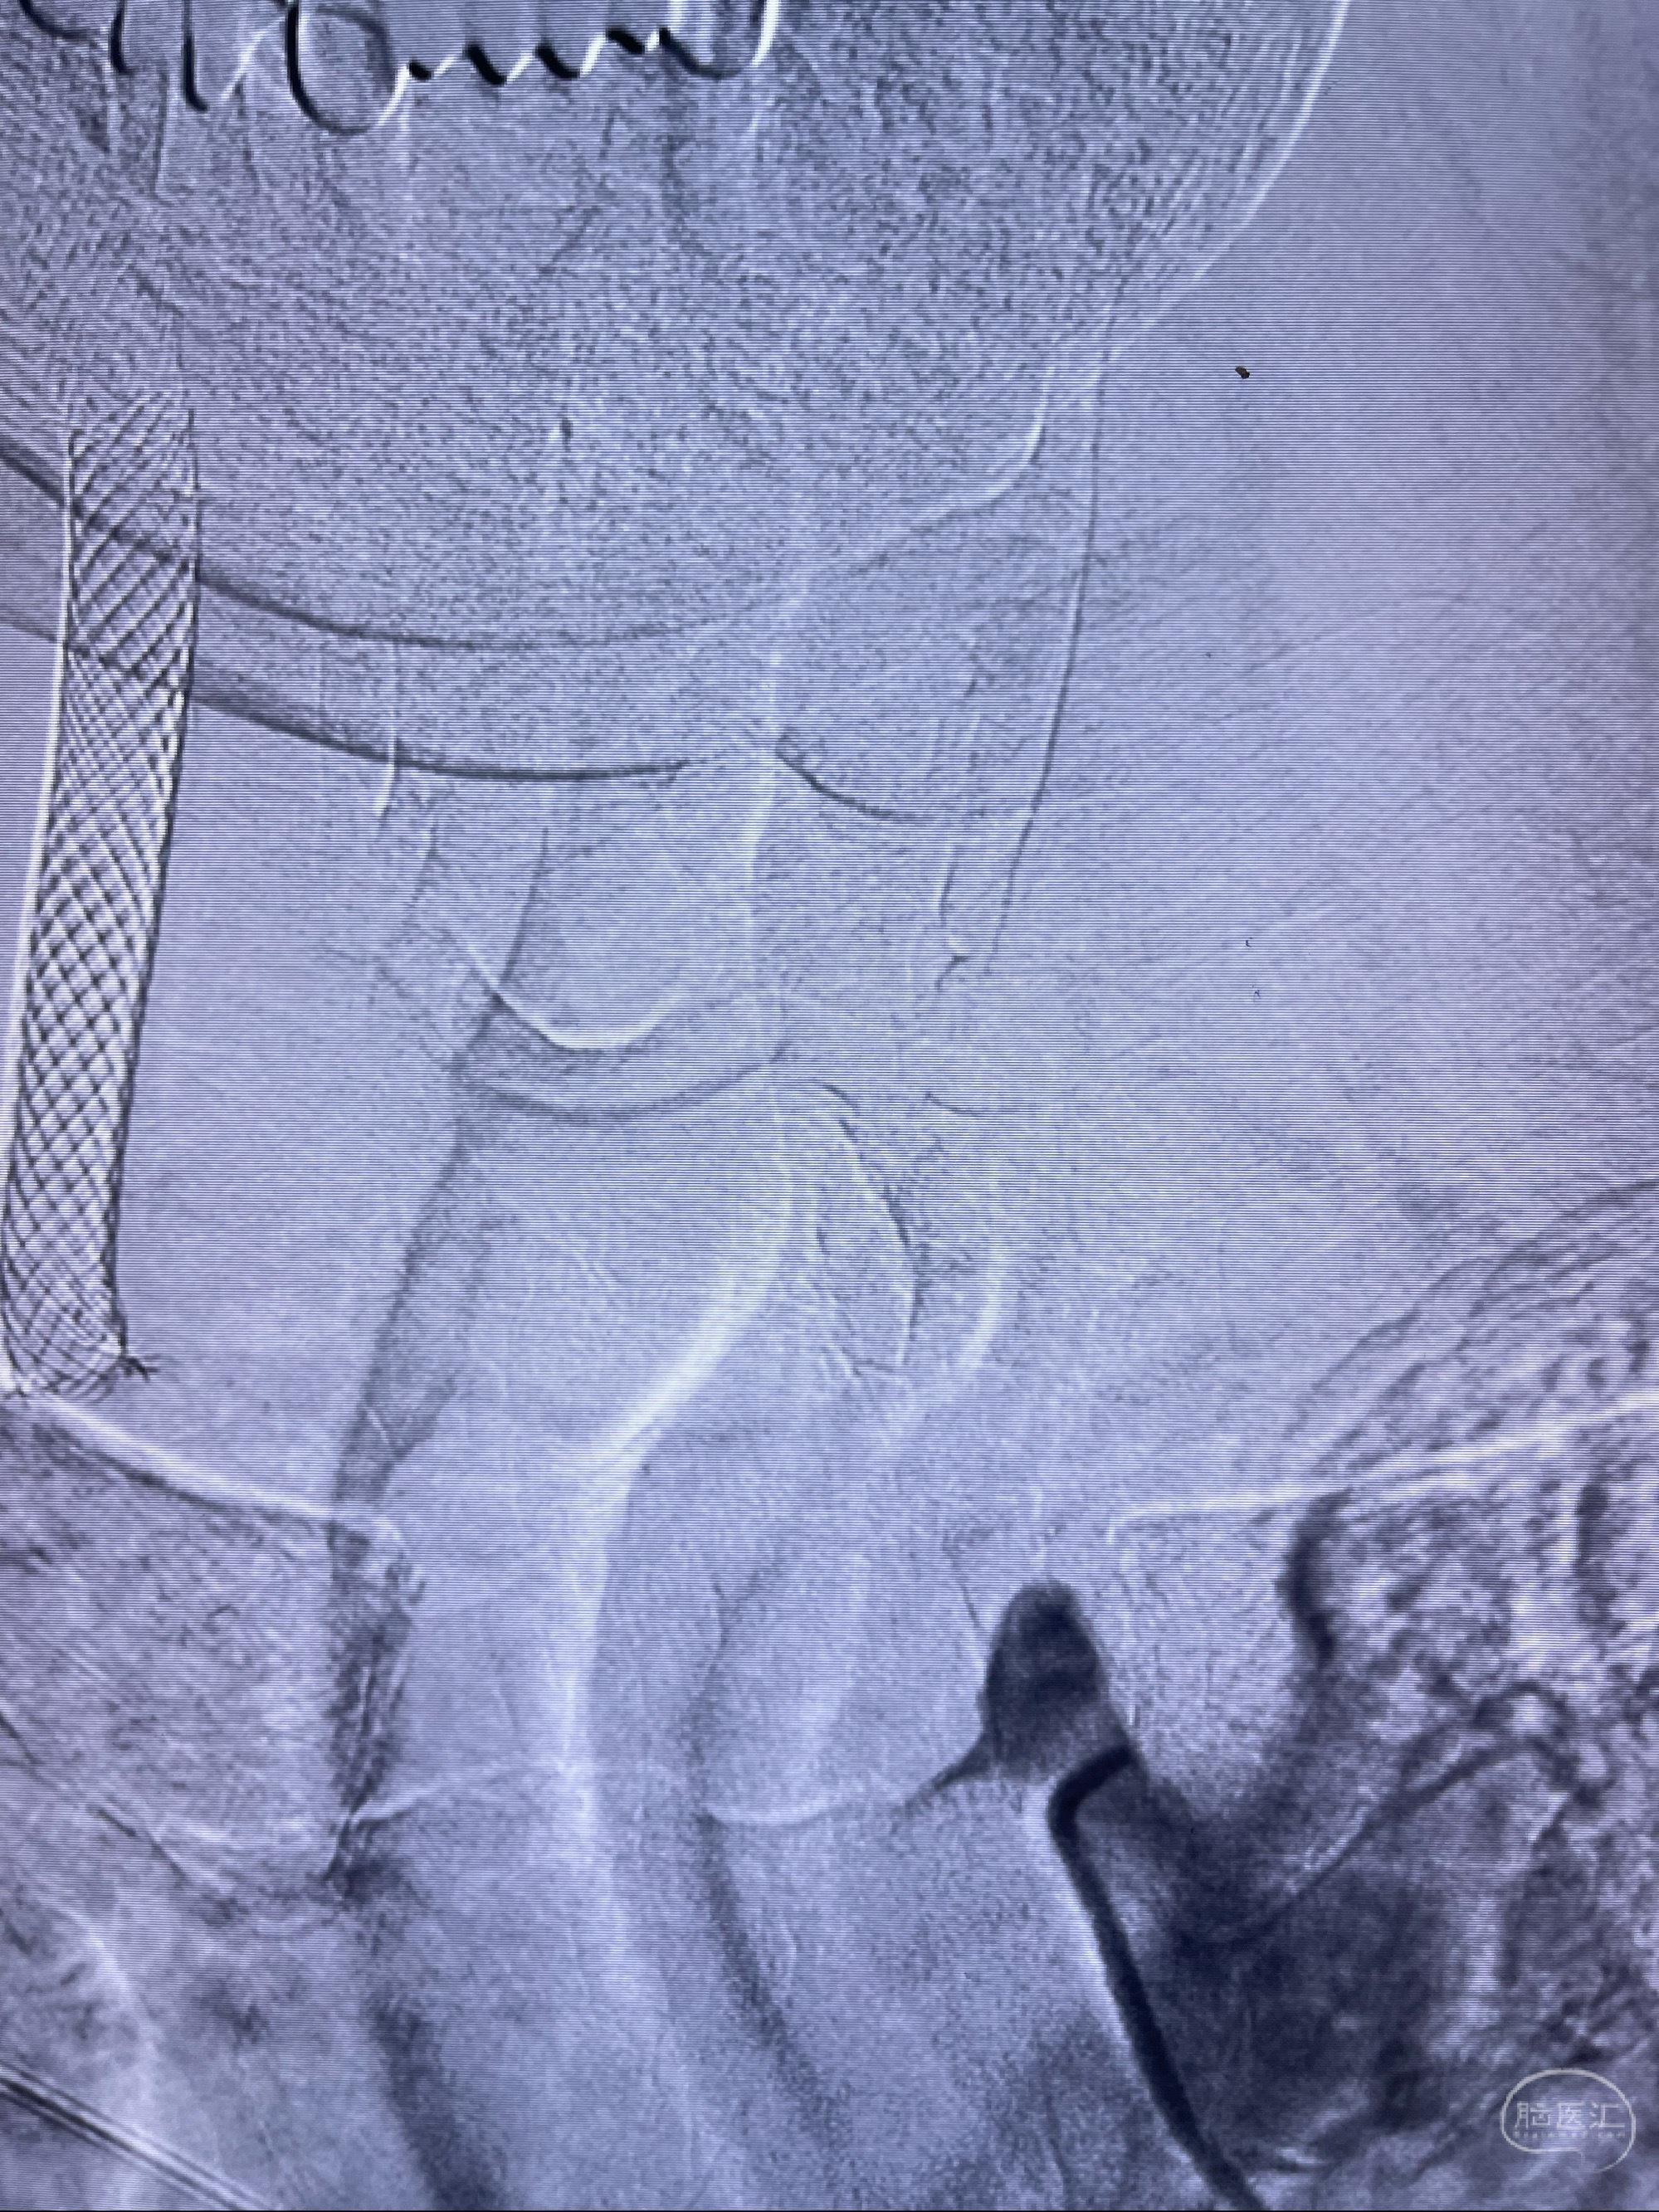

088NeuroMAX100cm长鞘在125cmMPA及黑泥鳅导丝引导下超选择性插入右侧颈内动脉支架内

经导引导管造影显示支架远端颈内动脉不规则狭窄伴局部充盈缺损,同时行全身肝素化5ml

路径图下4-20mm球囊在导丝引导下超选择性至狭窄段,以6-8个大气压扩张,持续30s

泄除球囊造影显示局部管腔扩张佳

后移球囊至颈段狭窄段,以8-12个大气压扩张,持续30s后泄除球囊

即刻造影显示狭窄扩张佳